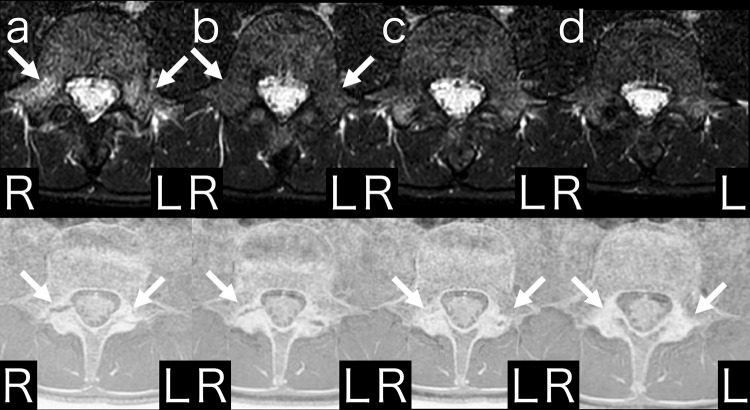

Multiple computed tomography (CT) scans are required to diagnose lumbar spondylolysis stage and confirm fusion degree. However, multiple CT scans should be avoided because of radiation exposure. There are no case reports of complete diagnosis and treatment of pediatric lumbar spondylolysis without the use of CT. Fast field echo resembling a CT using restricted echo-spacing (FRACTURE) is a magnetic resonance imaging (MRI) sequence used to evaluate bone lesions. Here we report the case of a pediatric patient with lumbar spondylolysis who was able to return to sports after diagnosis, treatment, and bone union confirmation using MRI and FRACTURE.